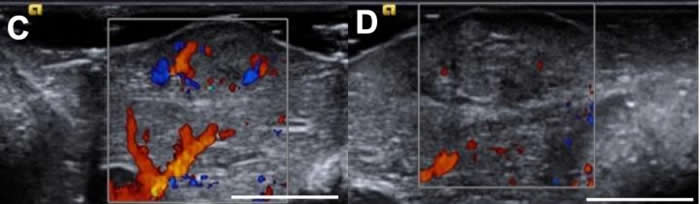

Hassan Albadawi和同事设计了一种名为LATTE的基于一种离子液体的替代消融术,它可将消融制剂和化疗药物直接输送至肿瘤内。该研究组发现,在HCC的大鼠和兔子模型中,单独注射LATTE或与化疗药物阿霉素联用可缩小肿瘤,并能在12个切下的人类肿瘤中快速杀死癌细胞。作者说:“我们预期,LATTE的安全特性、低成本、使用简单及可重复操作的灵活性均能令这一技术受到临床医师的青睐。”